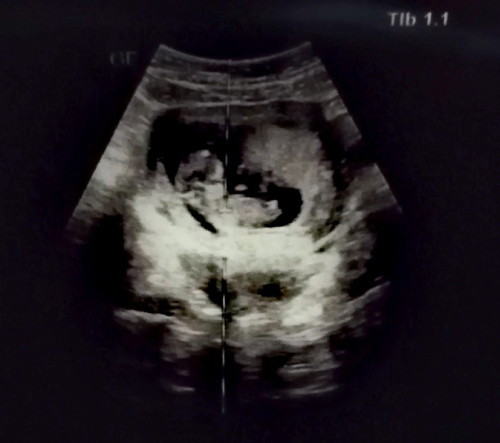

12วีค1วันค่ะ พึ่งซาวด์วันนี้เลยชัดมาก